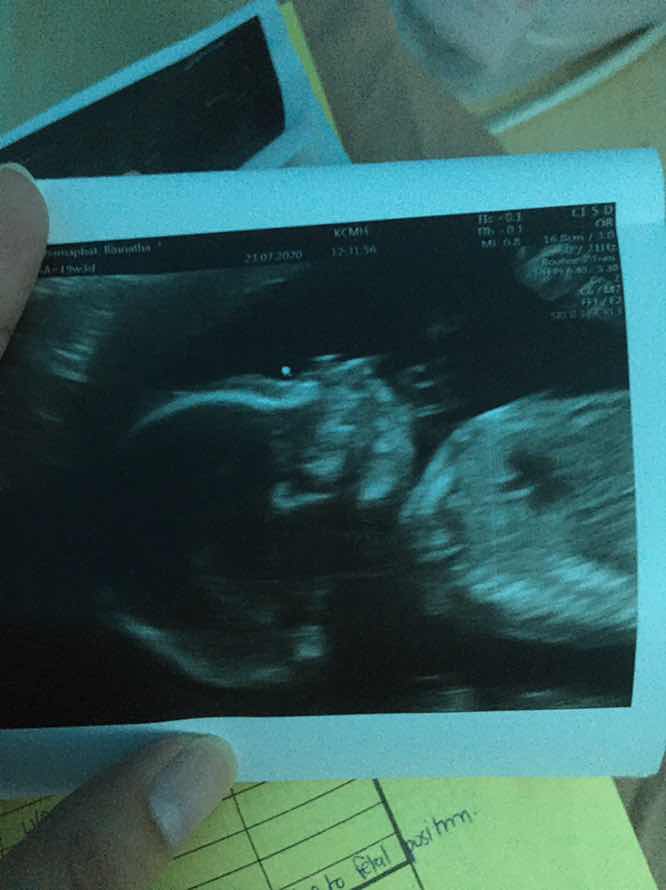

อายุครรภ์ 5 เดือน

สาวน้อย 5 เดือนของแม่ค่ะ โตขึ้นทุกวัน ตอดเก่งจริงๆ คือ ความสุขของแม่ ❤️ ตอนนี้หน้าตาเป็นยังไงกันบ้างล่ะคะ มาแชร์รูปอัลตราซาวด์เด็ก 5 เดือนกันค่ะ

หน้าตาเป็นแบบนี้จ้า 💙

20weeks ค่ะ ด้านข้าง